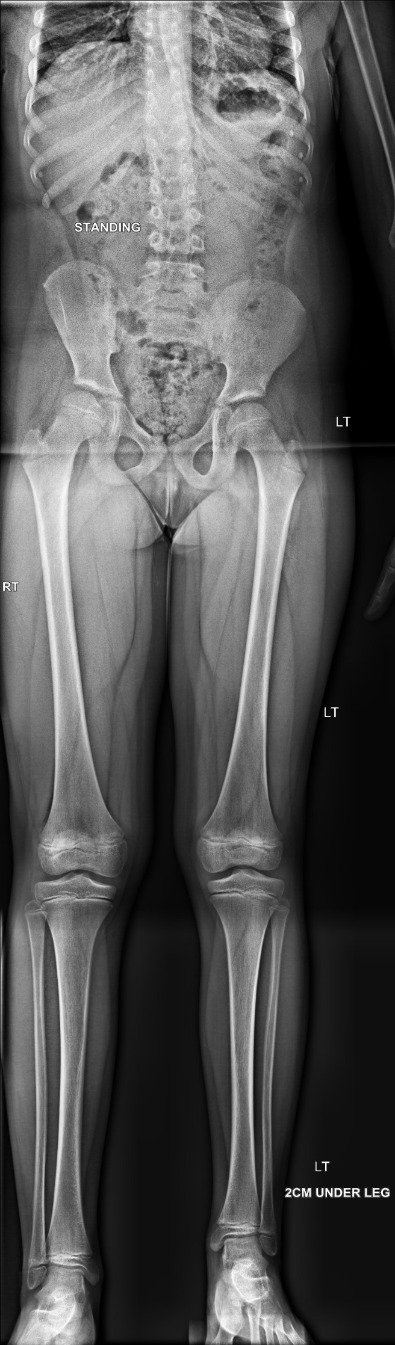

Leg length discrepancy

Leg length discrepancy is a difference between the lengths of the lower limbs. The causes vary and may include congenital, developmental, post-traumatic, infections, metabolic and neuromuscular causes. Mild leg length discrepancy is common and maybe considered as normal but a leg length discrepancy of more than two centimeters is likely to cause symptoms and the patient is offered surgical intervention. Surgery if required is ideally performed before the end of skeletal maturation.

The x-rays below show a case with shortening of the lower limbs (epiphysis).